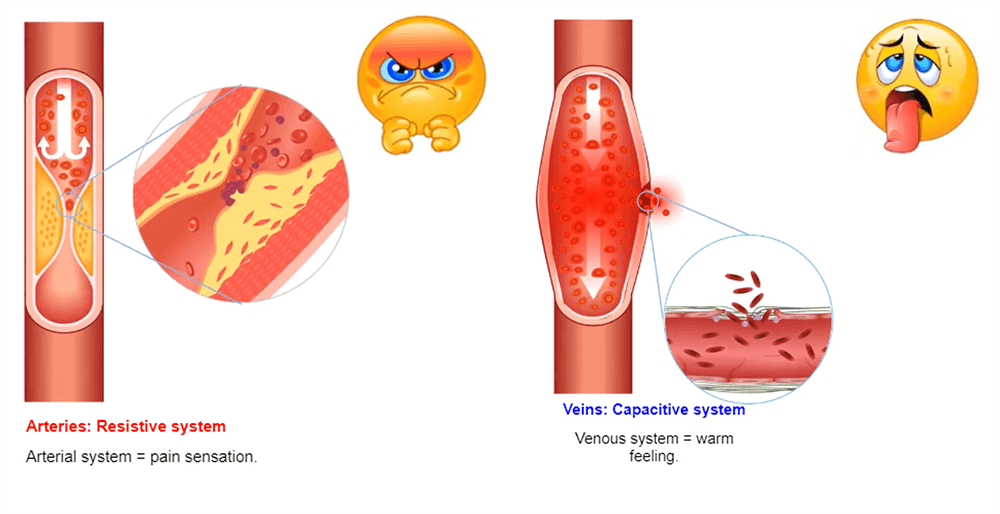

Osmolality

Osmolality refers to the number of particles present in a solution. Blood has an osmolality of 275-295 mosm/kg. Any solution with a higher osmolality than blood is considered hyperosmolar. Gadolinium has an osmolality of 630-1970 mosm/kg. The injection of a hyperosmolar product provokes a call for water from the interstitial to the interior of the vessel: this provokes hypervolume expansion.

The venous system is a capacitive system and it dilates easily causing a heat sensation. The arterial system is a resistive system, the vessel does not dilate easily, which causes a painful feeling.

In MRI, the amount of a substance given to the patient is very low and most of the time, the patients do not feel anything. But, it is always safe to use contrast with the lowest osmolality possible. The information about the contrast used in your facility can be found on the package insert with the contrast.